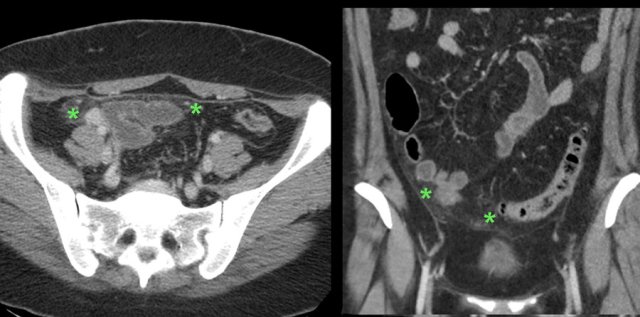

TOA case 2

Young

woman presenting with severe acute abdominal pain clinically suspect for perforated

appendicitis.

Lab-findings at admission: WBC 10.6 - CRP 6 Two days later: WBC 19.7 - CRP 459

US showed a large inhomogeneous masses left and

right of the uterus, suspect for tubo-ovarian abscess (TOA).

There

was also a paralytic ileus with secondary wall thickening of small bowel (b.) and

hyperechoic preperitoneal and mesenterial fat.

Puncture of a little ascites yielded

2 cc of yellow, turbid fluid.

CT

confirmed the US findings but additionally demonstrated a pyosalpinx (p.)

within the tubo-ovarian mass on the right side. Antibiotics are started intravenously.

Two

days later PCR of both cervical and urethral probes as well as the punctured

fluid were positive for Chlamydia.

Rapid recovery with only antibiotics.